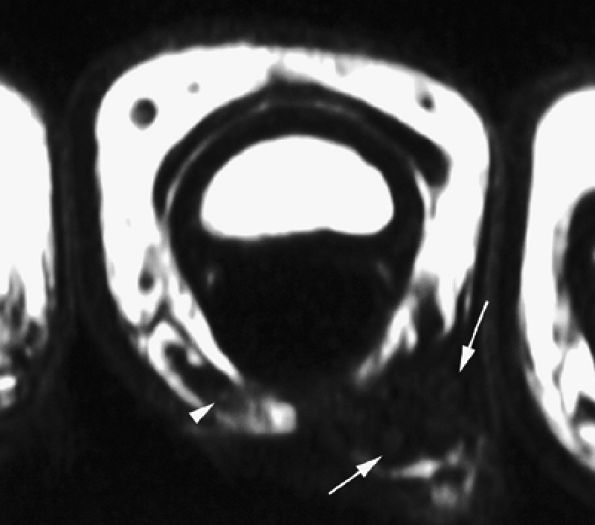

FIGURE 11.20 ● Acute injury of the radial collateral ligament (RCL) of the PIP joint of the fourth finger. Coronal (A) and axial (B) post-contrast fat-suppressed T1-weighted images displaying distal avulsion of the RCL with a proximal retraction (black arrows). The retinacular apparatus is displaced (arrowheads) with periligamentous edema. The ulnar collateral ligament is also identified (white arrows).